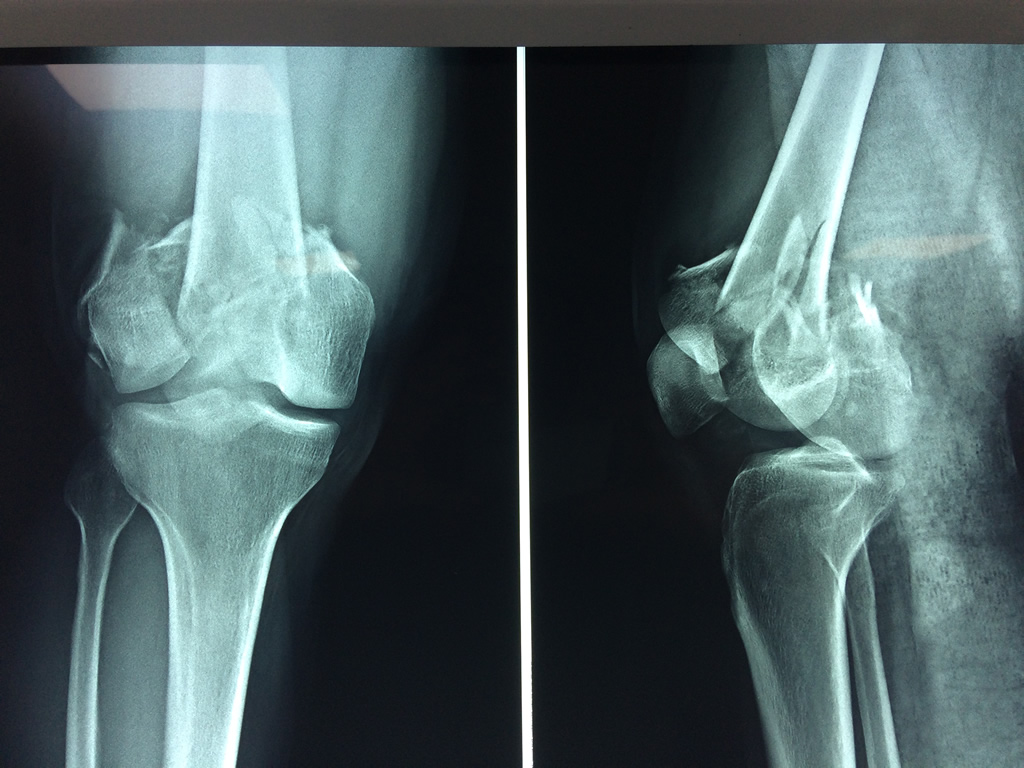

El fémur es el hueso del muslo, el segundo segmento del miembro inferior. Es el hueso más largo, fuerte y voluminoso del cuerpo humano.